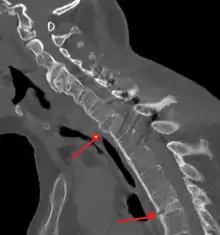

CT scan showing bamboo spine in ankylosing spondylitis